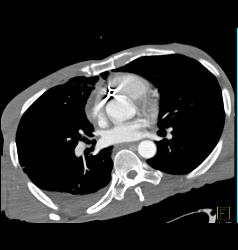

GSW With Bullet in Heart